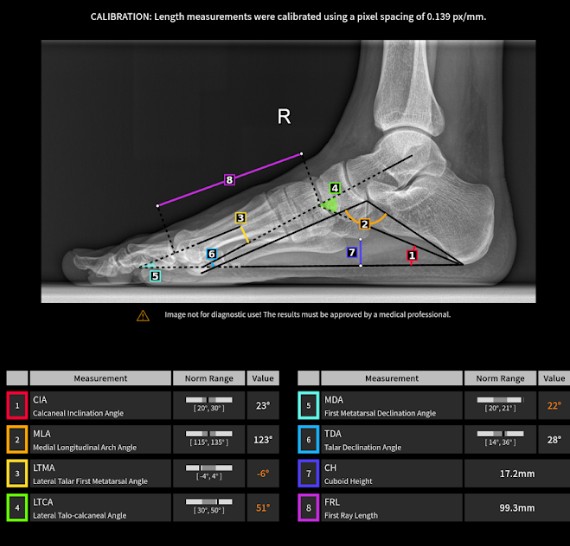

IB Lab FROG ist eine vollautomatische, radiologische Bildverarbeitungssoftware, die den Benutzer bei der Vermessung der Fußgeometrie auf Röntgenaufnahmen des Fußes unterstützen soll.

Die Ergebnisse werden in einem grafischen Befund zusammengefasst, dem Original-Röntgenbild beigefügt und automatisch im PACS-System gespeichert. Die KI erleichtert die Überwachung des Krankheitsverlaufs.

Radiologische Befunde, Messungen und Ergebnisse, einschließlich: